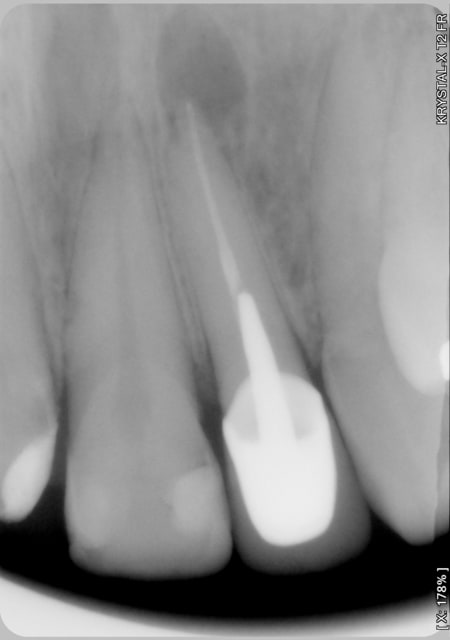

Sourire gingivale a mort, une CCM faite l'année derniere.

Morphotype epais et une bonne bande de gencive keratinisé.

Tout ce dont j'avais besoin pour changer un peu de la "routine" des resections apicales.

Mais apres analyse des photos jme suis dit que j'aurais du moins m'emballer sur la longueur !

Pour la technique c'est le lambeau d'ohsenbein lubke.

Il faut une bonne bande de gencive attaché(5mm), parodonte epais et comme ca t'évite les recession autour des jolies CCM que tu viens de faire.

Il faut bien maitriser ta technique chirurgicale pour aller vite. Tu sectionnes avec ce lambeau tout l'irrigation.